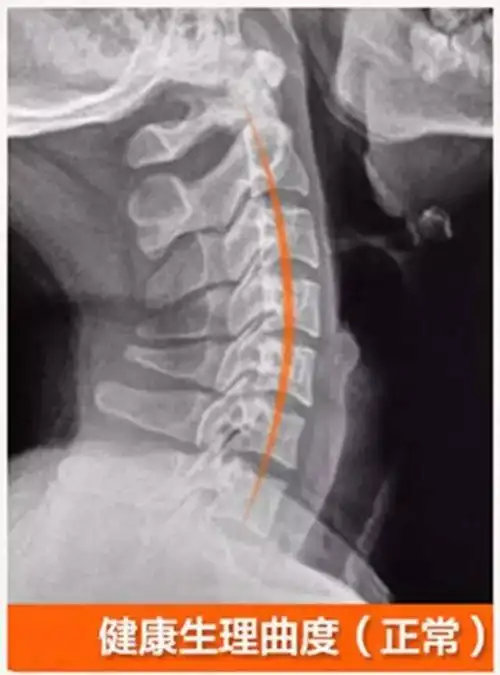

正常的人体脊椎生理弯曲图

注意一下你的颈椎弧度是否正确